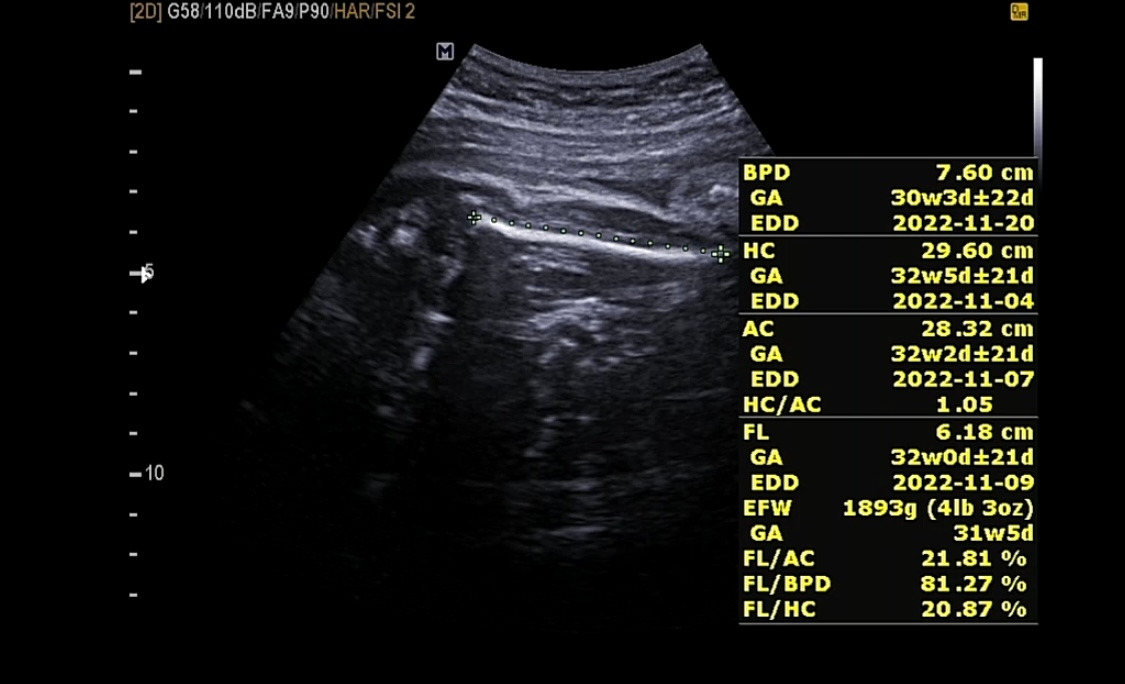

그 사이 궁금해서 남편과 함께 다른 병원을 방문했었다. 너무 오랫동안 다올이를 못 봤었기 때문에 얼마나 컸는지 궁금하기도 했고 어차피 백일해 주사를 맞으러 다른 병원을 갈 예정이었기 때문에 겸사겸사 다올이와 인사하고 왔다.

33주성장기록.png

그사이 열심히 커버린 우리 다올씨

기특하다 기특해